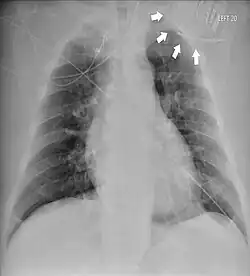

Das Twiddler-Syndrom ist eine seltene Komplikation nach dem Einbau eines Herzschrittmachers oder Defibrillators, bei der der Generator mit der Elektrodensonde (mehrfach) verdreht ist und die zur Funktionsstörung und Dislokation der Elektrode führt.[1][2]